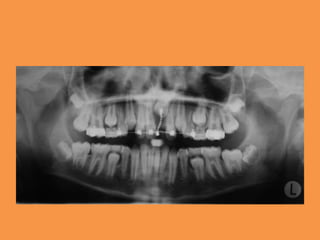

Figure 3: Panoramic radiograph

showing mild eruption of 11

Fig.1a-b Intra-oral photographs

Fig.2 Panoramic radiograph showing

impacted maxillary central

incisor and mesiodens in region of 21

Figure 3: Panoramicradiograph showing mild eruption of 11

Fig.2 Panoramic radiographshowing impacted maxillary central incisor and mesiodens in region of 21